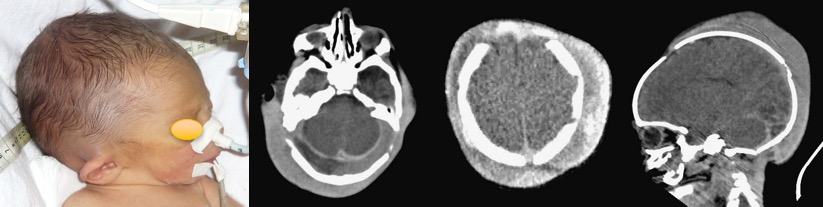

il s’agit d’une collection volumineuse qui déforme le cuir chevelu, parfois soulève le lobule de l’oreille, et provoque une anémie aiguë et une CIVD chez le nouveau-né.

l’hématome sous-galéal sous pression peut compromettre la vitalité du cuir chevelu et entraîner une nécrose. même dans le cas extrême montré ci-contre, la capacité de reconstitution spontanée d’un cuir chevelu complet (avec ses annexes) est frappante.